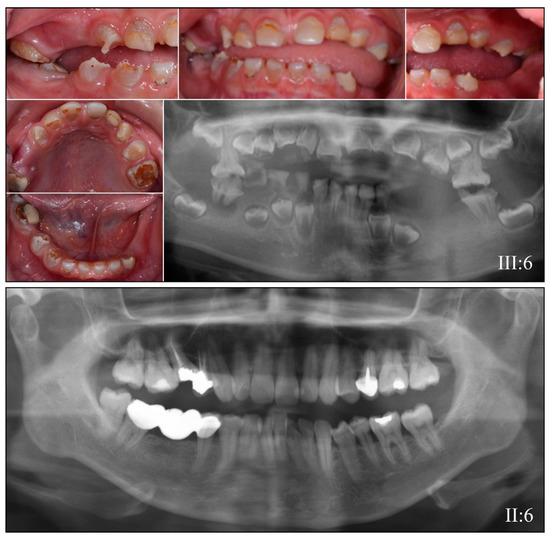

3.2. Four Families with DGI-III: 5′ DSPP Mutations

| 1 | Illumina HiSeq 2500 (WES) | NG_011595.1:g.7430C>T; NM_014208.3:c.50C>T; NP_055023.2:p.(Pro17Leu) | Missense | II:6, unaffected mother: 136.75× III:5, affected 1st child: 159.3× III:6, affected 2nd child: 129.86× |